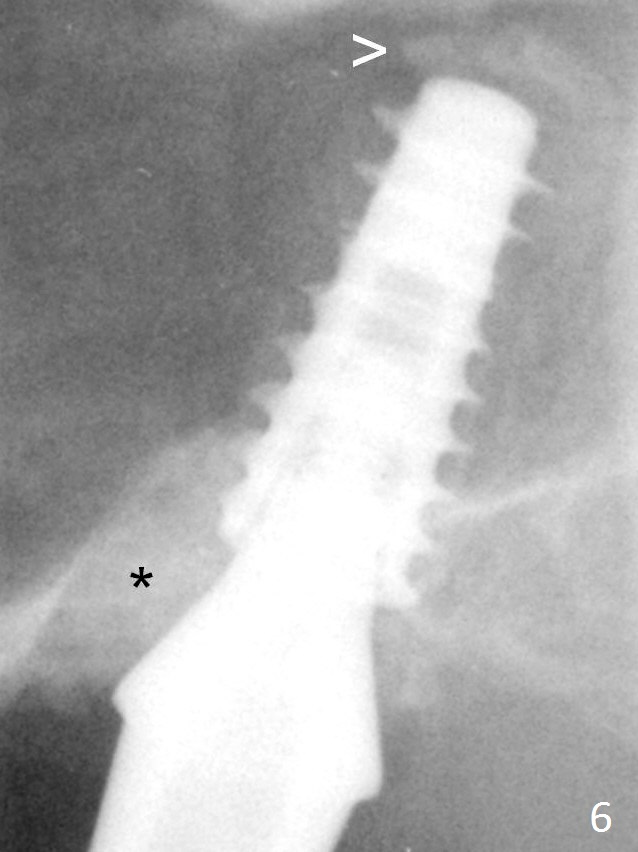

There is bone formation in the sinus distal to the implant 6 months post cementation (Fig.14 *) with the osseous tissue having grown into between the threads (arrow).